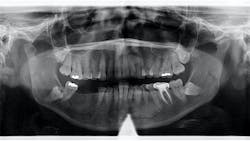

A panoramic radiograph revealed an almost-vague radiodense lesion on the lower left side, around the apices of teeth nos. 20–22, measuring approximately 3 cm x 1.5 cm. The lesion was nonpalpable, the area was not tender to palpation, and the patient was unaware of its presence.

Definitive diagnosis: Idiopathic osteosclerosis

Since this patient presented with no neurosensory changes, cortical expansion or displacement or resorption of adjacent teeth, and its cause could not be readily explained, it is consistent with a diagnosis of idiopathic osteosclerosis. The patient continues to be recalled periodically to assess for changes in this area.